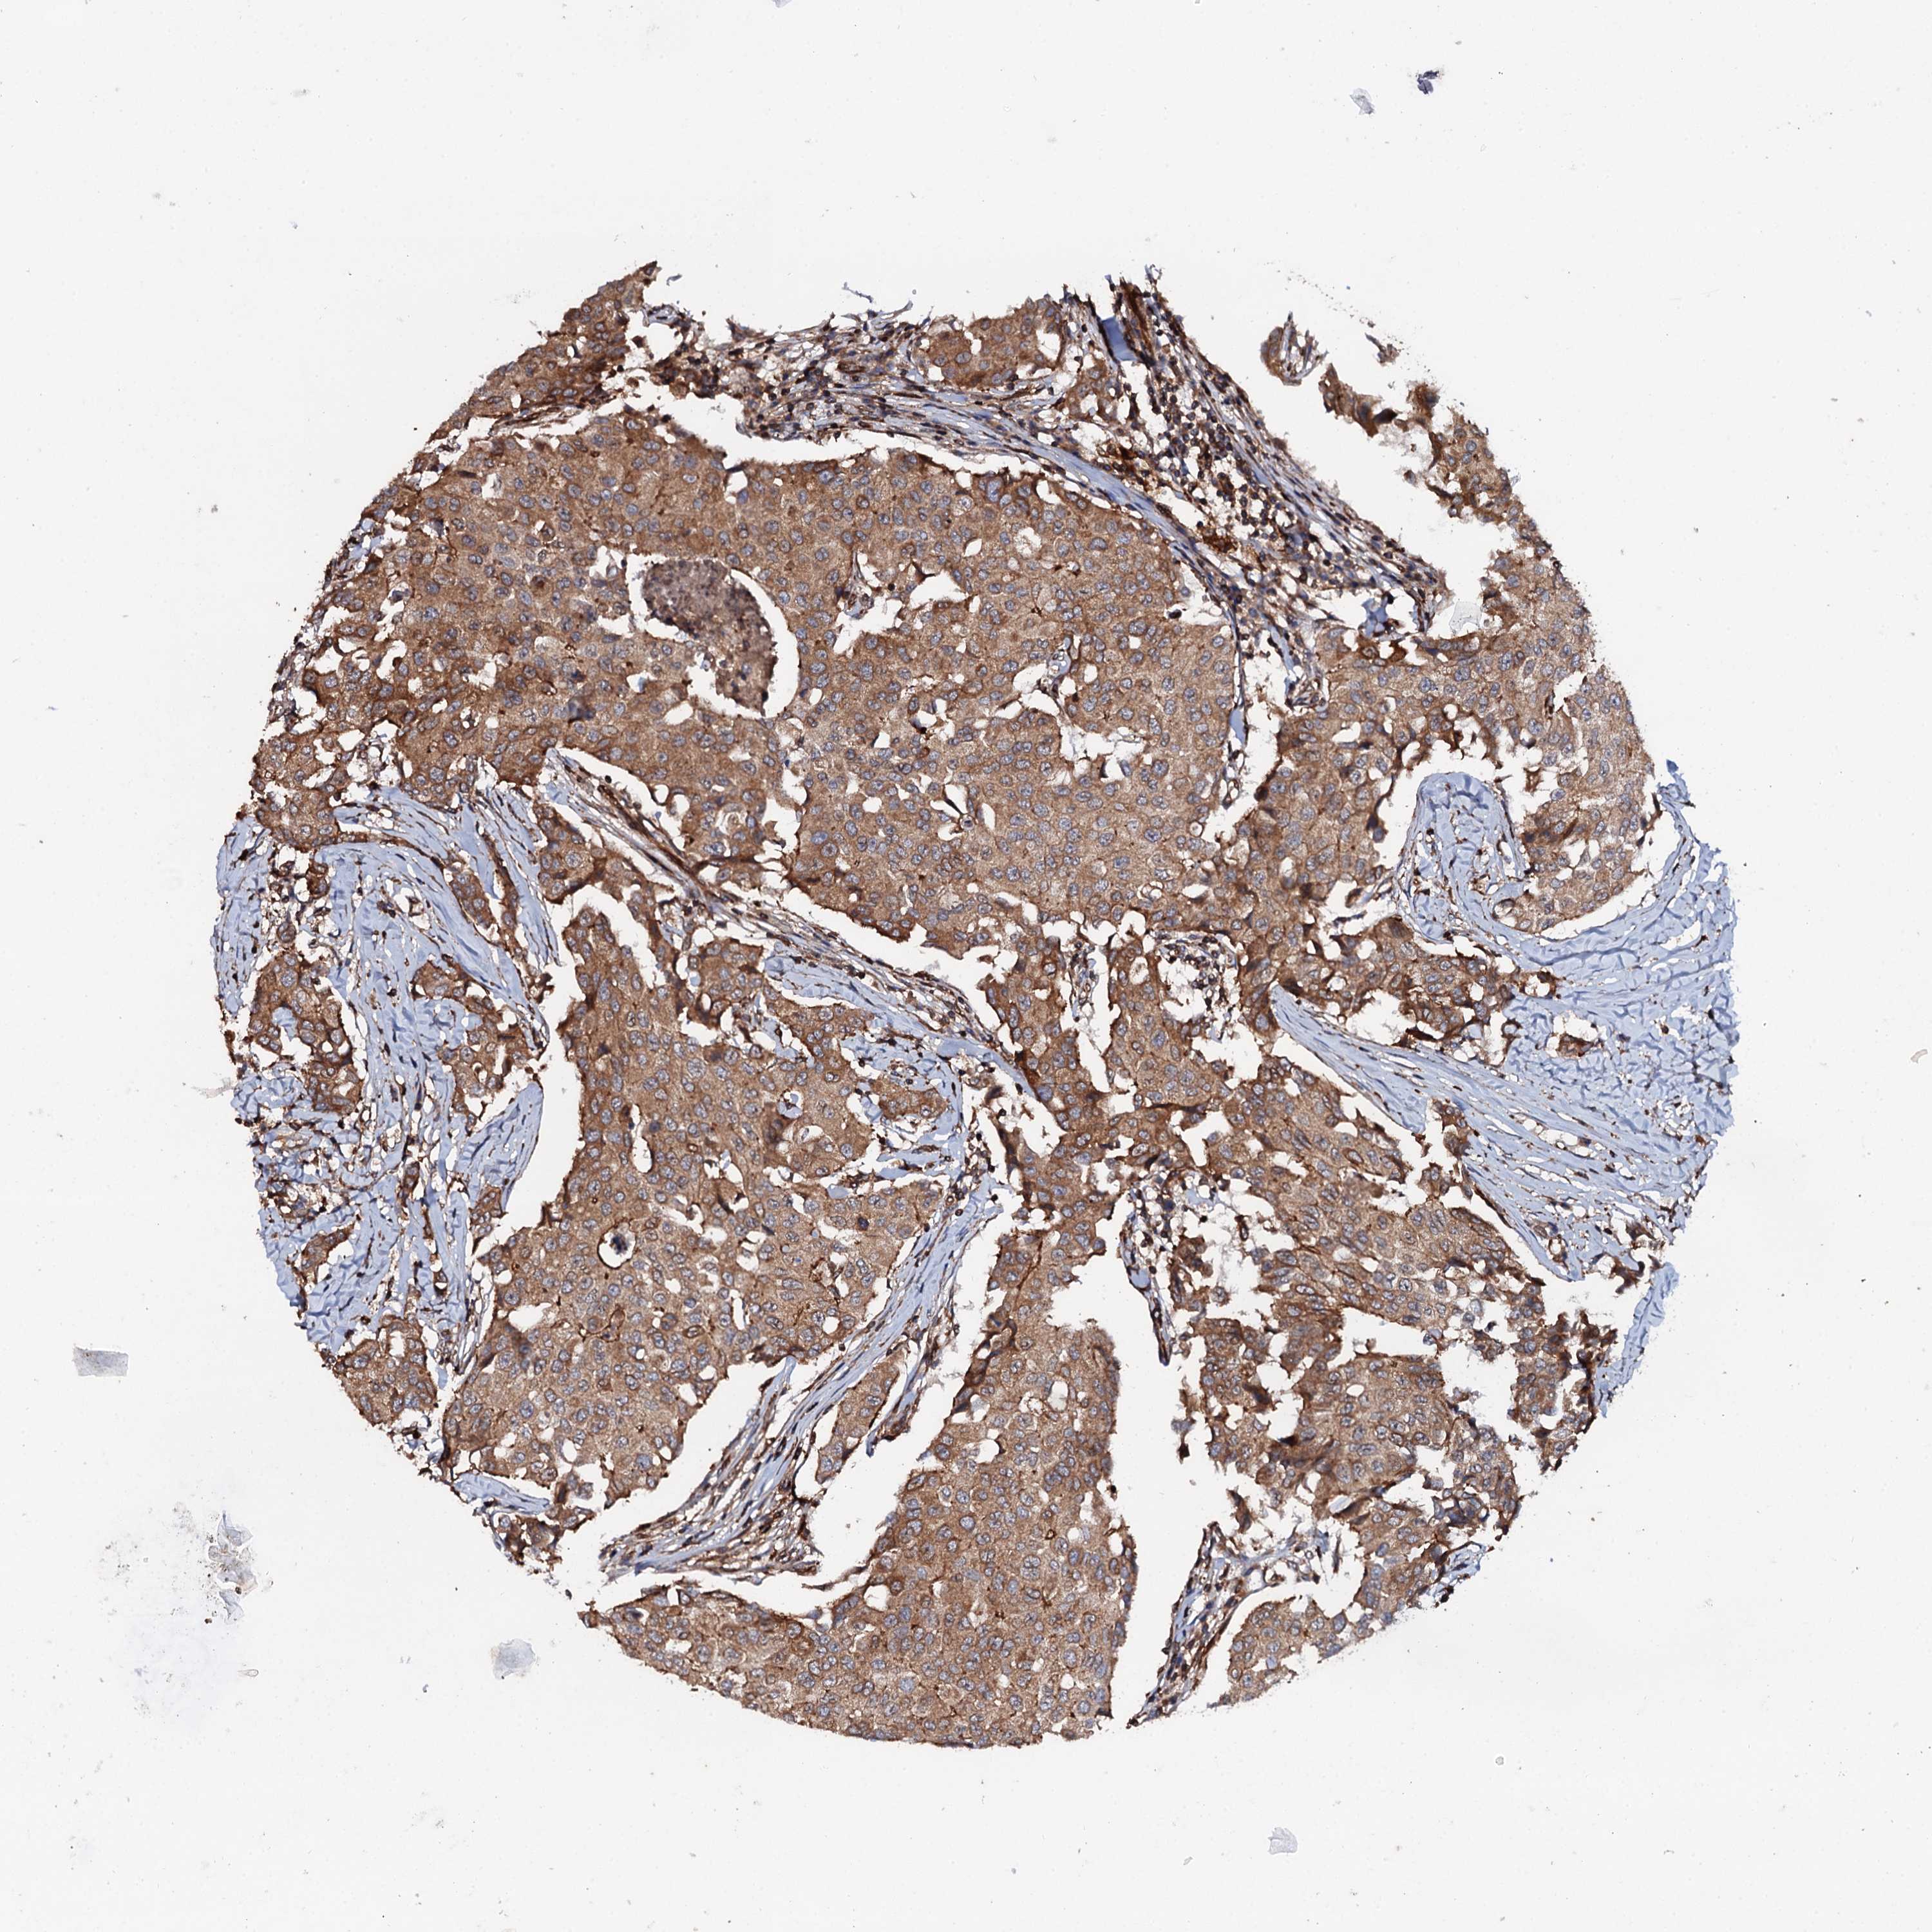

CANCER BREAST CANCER Show tissue menu

BRCA TCGA BRCA VALIDATION PROTEIN EXPRESSION